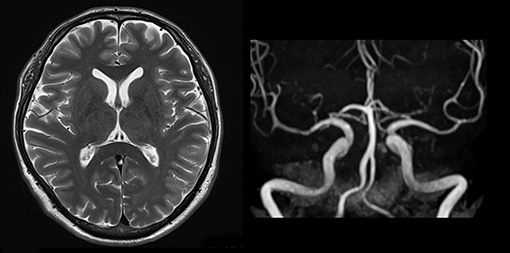

頭部MRI検査

| 30分 | MRI検査:頭部MRI・頭頚部MRA |